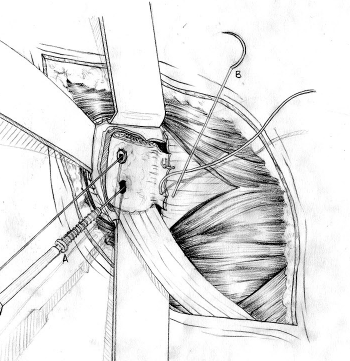

Transfer of coracoid process and conjoint tendon through subscapularis

- split subscapularis at midsubstance of muscle belly

- can perform subscapularis tenotomy

- capsulotomy - vertical or transverse

- medial glenoid retractors / Fukuda retractor over humeral head

- inferior glenoid retractor - protect AXN

Secure coracoid

- inferior half of glenoid

- no medial overhang

- secure with 2 x bicortical screws with compression

Closure capsule / subscapularis